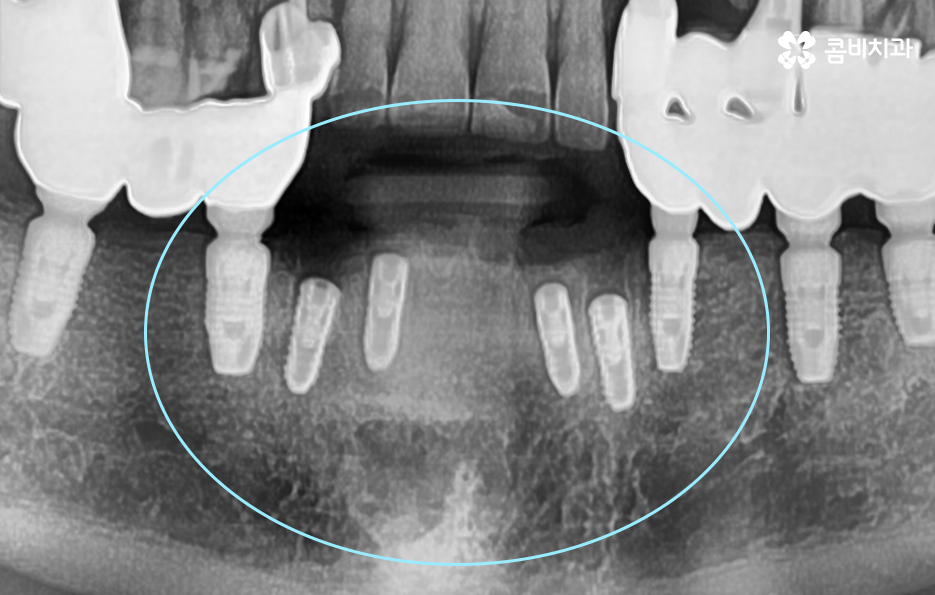

위 사진에서 보시는 것처럼 이미 치주염으로 인해 뿌리가 흔들리는 치아는 한꺼번에 여러 치아를 잃게 되었으며 기존의 임플란트 역시도 약해진 잇몸 뼈와 치료 비용 등을 감안하여 브릿지의 형태로 임플란트가 식립되어 있는 것을 확인할 수 있어요